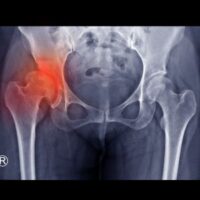

The first step is to properly diagnose your dislocated hip. You can do this by seeing a medical professional immediately after the workplace accident. Doctors usually identify dislocated hips with X-rays and physical examinations.